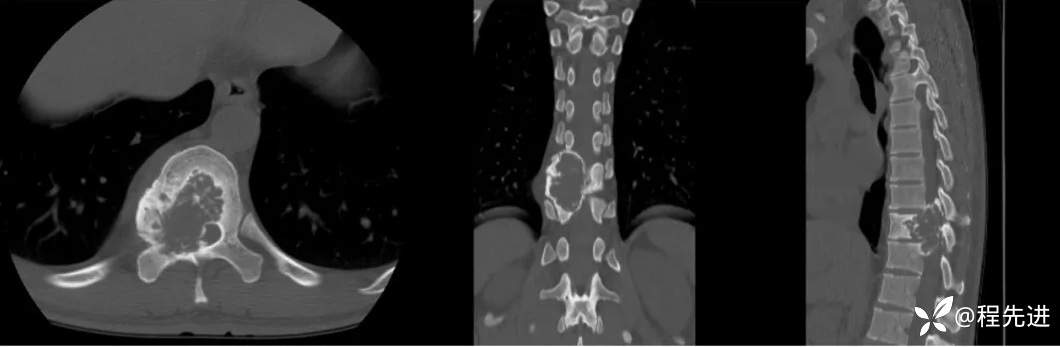

【患者信息】:男,29岁

【现病史及既往史】:双下肢麻木无力5月余,有踩棉感

【检查】